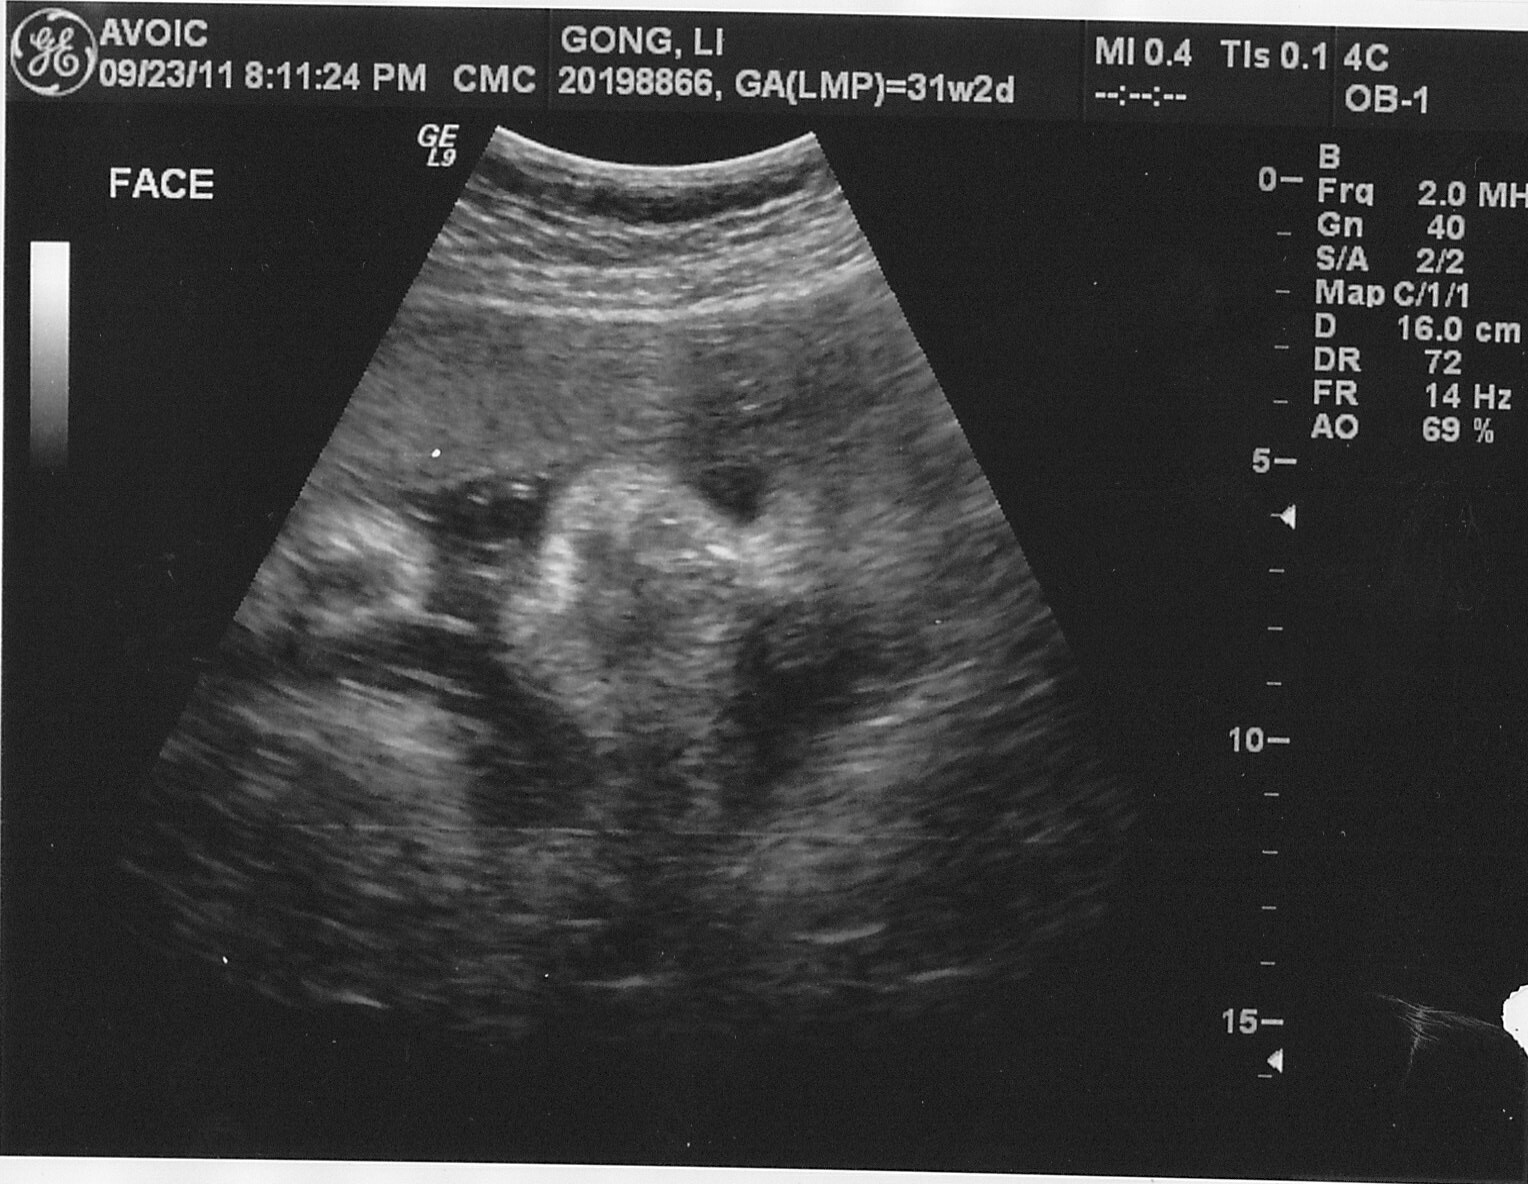

The most amazing part of this ultrasound is that I can actually see the baby’s face!!

face